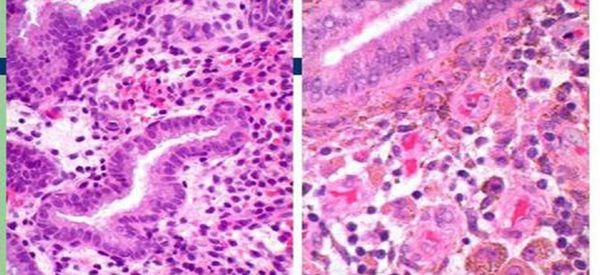

很多妹子都有痛经的毛病,原本嘻嘻哈哈的人,来个月经就能被打倒,这着实让人沮丧。虽然痛经很常见,痛经也可能提示疾病。痛经就是子宫内膜异位症的重要表现之一。子宫内膜..